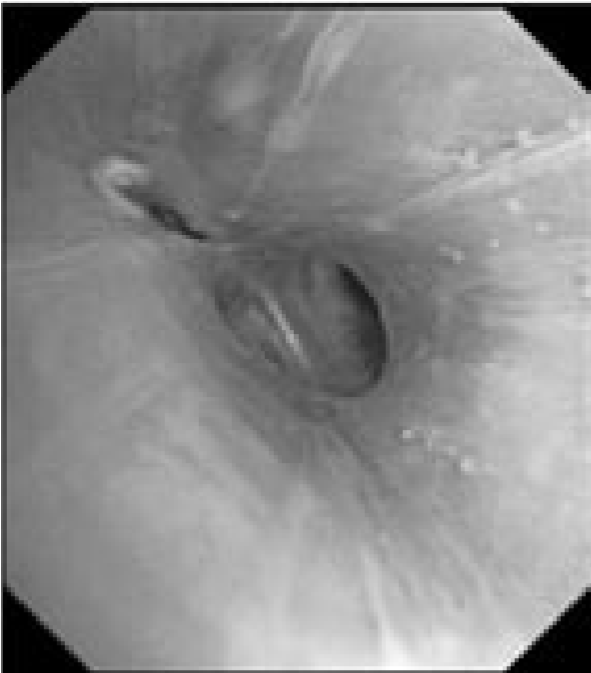

В связи с сочетанным характером патологии (поражение как легочной ткани, так и средостения) было запланировано проведение комбинированного двухэтапного эндоскопического исследования. На первом этапе предполагалось выполнить видеобронхоскопию в стандартном разрешении с детальным осмотром верхнезонального бронха левого легкого, бронхоальвеолярный лаваж (БАЛ), при наличии технической возможности – браш-биопсию и щипцовую трансбронхиальную биопсию легкого. На втором этапе планировалось провести эндоскопическую ультрасонографию средостения эхобронхоскопом (ЭУС-б) с визуализацией бифуркационного лимфоузла с последующей тонкоигольной пункцией. Все исследования планировалось осуществить в условиях местной анестезии. 23.08.2017 г. пациенту выполнена видеобронхоскопия бронхоскопом Olympus BF 1Т150 (Olympus Corp., Japan). Интубация проведена через правый носовой ход. По результатам исследования гортань без особенностей. Трахея свободна, отделяемого нет. Бифуркация не расширена, карина острая, подвижная, устья бронхов 1–5-го порядка справа открыты, не деформированы, в просвете сегментарных бронхов единичные комочки слизистой мокроты. Слизистая видимых бронхов справа несколько отечна, гиперемирована. Слева: при осмотре бронхов верхней доли определяется перибронхиальный стеноз устья LВ1-2 до 3 степени, признаков пролиферативного поражения слизистой в указанной зоне нет. При акваскопии – устье стенозированного бронха открывается, признаков специфического поражения слизистой не выявлено. Слизистая бронхов слева умеренно гиперемирована, отечна (рис. 2).2

Рис. 2. Видеобронхоскопия пациента А., эндофото:

а – шпора верхнедолевого бронха левого легкого, визуализируется просвет нижнедолевого бронха (на 6 часов), на 12 часов – устья язычковых бронхов и верхнезонального бронха левого легкого; б – устье верхнезонального бронха левого легкого (LB1-2 и LB3), четко визуализируется продольный характер складчатости слизистой; в – детальный осмотр ветвей верхнезонального бронха: визуализируется перибронхиальное сужение устья LB1-2 до практически полного исчезновения просвета, дистальные ветви данного бронха осмотру недоступны, устье LB3 без особенностей, отмечается точечная пигментация слизистой над устьем LB1-2; г – осмотр устья бронха LB1-2 с помощью акваскопии (введение лаважного раствора в устье бронха под давлением) – признаков опухолевого либо специфического (туберкулезного) поражения слизистой не выявлено; д – осмотр устья бронха LB1-2 после выполнения акваскопии и забора БАЛ – скудное поступление пенистого отделяемого (по сравнению с активным дренажом из устья LB3 – на 4 часа); е – попытка выполнения щипцовой трансбронхиальной биопсии через устье LB1-2 (визуализируются бранши биопсийных щипцов – на 4 часа).

Пациенту выполнен комплекс биопсий в объеме: БАЛ через LВ1-2 (крайне скудный возврат), браш-биопсия там же. Проведение щипцовой биопсии в указанной зоне оказалось технически невозможным (высокий уровень отхождения бронха). Полученный диагностический материал был направлен на цитологическое и микробиологическое исследования (люминесцентная микроскопия, молекулярно-генетическое исследование, посев на жидкие питательные среды на МБТ) для верификации диагноза. Эндоскопическое заключение: Стеноз устья LВ1-2 до 3 степени, перибронхиальная форма. Диффузный двусторонний неспецифический бронхит 2 степени2